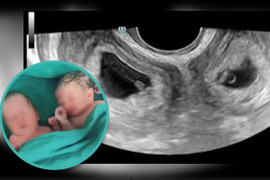

Một người phụ nữ ở Trung Quốc vừa sinh hai con, gồm một trai và một gái từ hai tử cung khác nhau có trong cơ thể cô.

Ca mang thai đôi hy hữu một con mình, một con người khác xảy ra do trong quá trình mang thai hộ, người phụ nữ đồng thời có thai với chồng.

Sau 37 tuần mang thai khỏe mạnh, bà mẹ 9X này đã sinh thường thành công hai bé trai bụ bẫm, một bé 2,9kg và một bé 3kg.